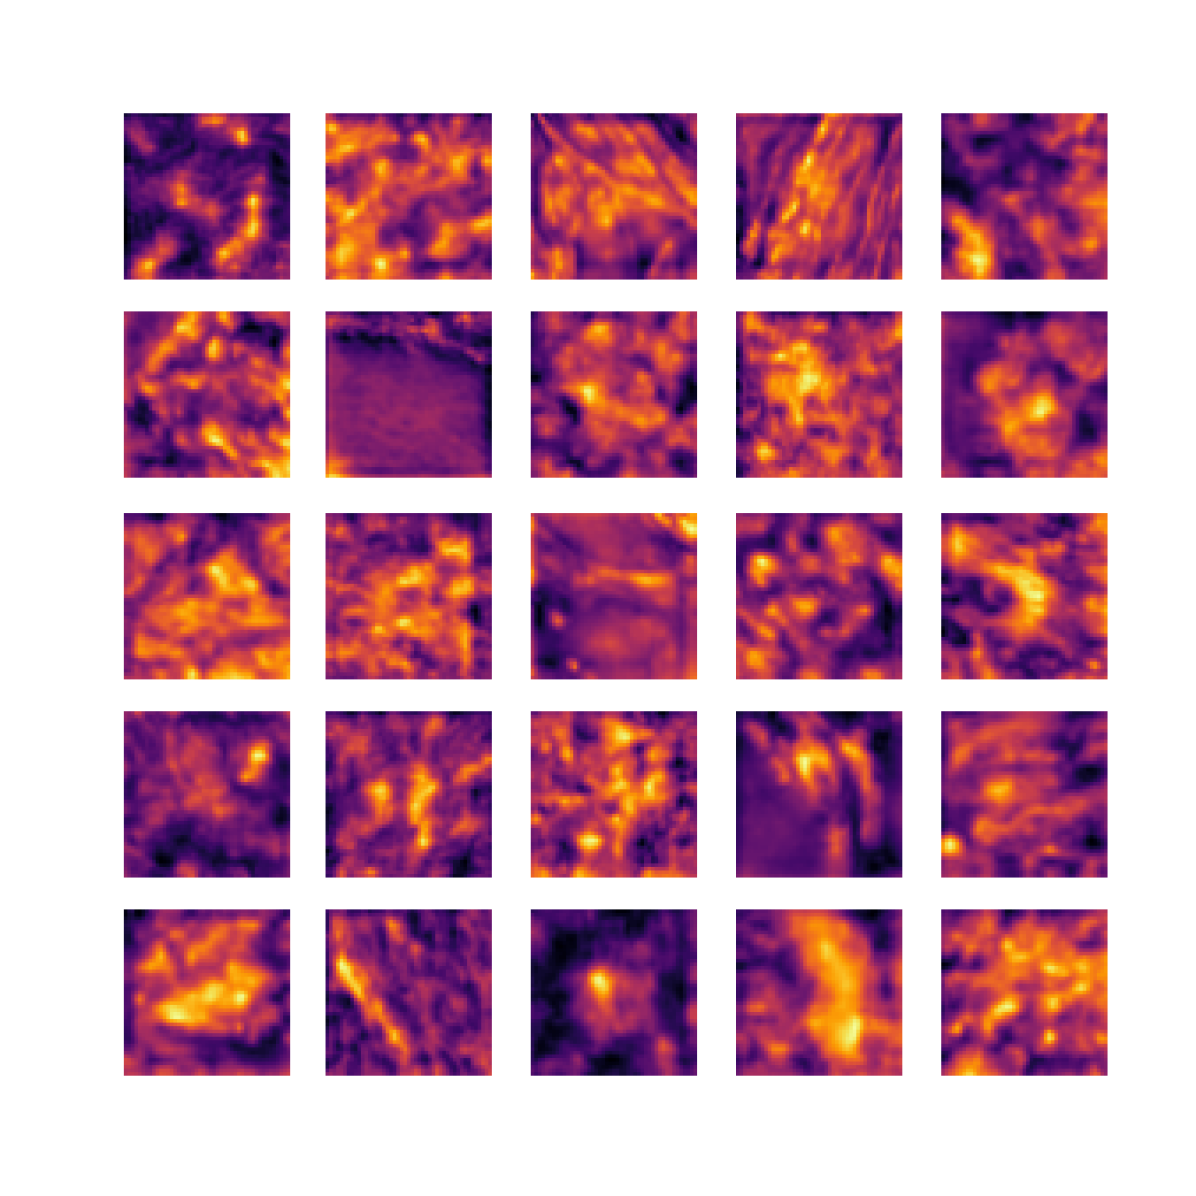

We also analyse the activation maps for each model using GradCAM as described in section S3. This offers more insight into the areas of the image which are contributing most heavily to the models’ representations. In Figure 4(b) we present some representative examples, however, a larger selection which was chosen at random is presented in Figures S10 to S25. The larger selection makes it easier to see the emergent patterns, including that privileged Siamese models tend to mainly identify features which are strongly present in both inputs, while unprivileged Siamese models tend to learn more diffuse features that are not specific to one cell phenotype or image region. TriDeNT ♆ incorporates both sets of features, learning both features specific to the privileged data and more the general features associated with unprivileged Siamese networks.

We can see in Figure 4(b) panel A that for ERG, the privileged Siamese model focuses almost exclusively on any nuclei which could be endothelial cells. As there are very few endothelial cells in the dataset, it could be an effective strategy to identify anything that could potentially be an endothelial cell to minimise the difference between the representations of the H&E model and the IF mask model. In the corresponding unprivileged Siamese image, we see that the model identifies some of these nuclei, albeit less strongly, but also focuses heavily on the other tissue and even the background, while strongly fixating on two spots of debris in the center of the image. This model has less ‘incentive’ to learn the weak features related to endothelial cells as these occur rarely and are not easy to detect, while more generic strong features such as the presence of connective tissue and the prevalence of background are more common and predictable from augmented images. We see that TriDeNT ♆ combines these two feature sets, strongly identifying nuclei while also identifying the connective tissue.

In panel C we see a similar pattern, with the privileged Siamese model fixating solely on the nuclei, while the TriDeNT ♆ model takes a more balanced approach. The unprivileged Siamese model appears to focus on a single cluster of nuclei while neglecting others, and similarly identifies an area of fibroblasts with its distinctive pattern but does not others.

In contrast to panels A and C which represent models with poor privileged Siamese results, panels B and D represent models whose privileged Siamese results were comparable to both TriDeNT ♆ and even the supervised baseline. It is therefore interesting to note that there are far more similarities between the privileged Siamese and TriDeNT ♆ models in both cases. Particularly in panel B, TriDeNT ♆ and the privileged Siamese model return virtually identical heatmaps, with both strongly identifying epithelial nuclei and neglecting the same areas of connective tissue. The unprivileged model in this case appears to focus solely on the centre of the image, giving a significantly different heatmap to the other panels.

Panel D again shows the previous pattern, with the privileged Siamese model identifying the features strongly present in the privileged data – fibroblasts – while neglecting the nuclei present. TriDeNT ♆ also strongly identifies the connective tissue, but, unlike the privileged Siamese model, does not completely neglect the nuclei. The unprivileged Siamese model primarily identifies background, and does not appear to identify the nuclei in this example.